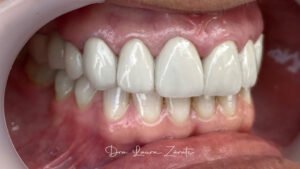

Decidí recuperar mi sonrisa y fui a la clínica dental donde me atendió la Dra. Laura Zárate. Me explico paso a paso como sería el procedimiento. Resolvió todas mis dudas y me dio la confianza para iniciar el tratamiento.

Hoy, gracias a mi prótesis híbrida, puedo reír, comer y hablar con total naturalidad. Recuperé mi sonrisa, mi confianza, mi alegría. Hoy puedo decir que recupere mi calidad de vida